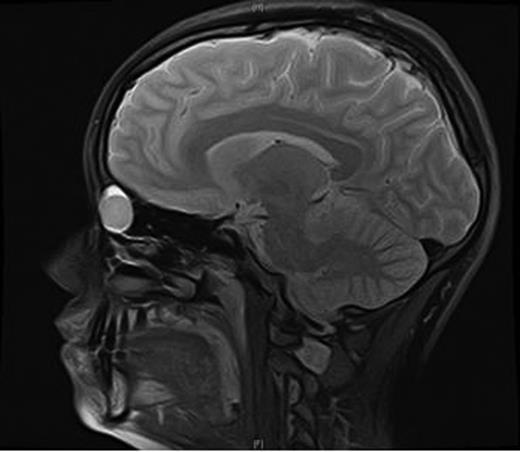

Clinical examination revealed a small cystic swelling in her left medial canthus (Fig. 1). There was no discharge on pressure, mild tenderness was elicited and the swelling was not compressible. The rest of the eye examination was normal with a visual acuity of 6/6 in both eyes.

An MRI scan of the orbits showed a well-defined, thin-walled 22 × 16 mm cyst medial to the left orbit containing fatty/proteinaceous material, which was lying within and mildly expanding the left ethmoid air cells (Figs 1–3).